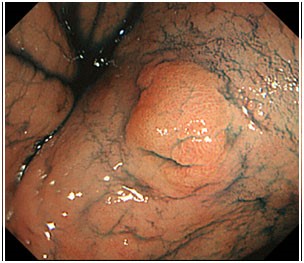

Erken teşhis konulmasına bir diğer önemli uygulama boyama yöntemidir. Bu yöntemde mide içeriği tümü ile aspire edilip yıkandıktan sonra, mide mukoazası özel boyalarla boyanır. Kanser hücreleri boyayı az tutar. Halbuki normal mide mukozası hücreleri homojen şekilde boyanır. Bu durum işlem sırasında boyayı az tutan kanser hücrelerinin tanınmasını sağlar. Kanser hücrelerinin diğer bir özelliği de boyama sonrası yıkama yapıldığında, tuttuğu boyayı bırakmaz. Normal mide mukoza hücreleri ise boyama sonrası yıkama yapıldığında boya maddesini tümü ile bırakır ve homojen bir görüntü verir. Bu özellik de yine kanser hücrelerinin tanınmasını kolaylaştırıcı önemli bir faktördür. Sonuç olarak boyama yöntemi kanser hücrelerini endoskopi işlemi sırasında tanınır hale getirir, biyopsi alınarak ve tanı konulmasını sağlar.

Biz yaptığımız endoskopik incelemelerde, muayene öncesinde mutlaka hastada geniş bir sorgulama yapmaktayız ve eğer varsa risk faktörlerini ortaya koymaktayız. Riskli grupdaki hastalara ve mide kanseri alarm semptomlarına sahip olan hastalarımızda mutlaka boyama tekniğini kullanıyoruz. Bu şekilde mide kanserini erken evrede yakalamak mümkün olmaktadır. Erken evrede yakaladığımız mide kanseri hastalarımızı çok büyük cerrahi ameliyatlara gerek kalmadan endoskopik submukozal diseksiyon tekniği ile tedavi etmekteyiz. Boyama öncesi ve sonrası elde edilen bazı görüntüler aşağıda sunulmuştur.